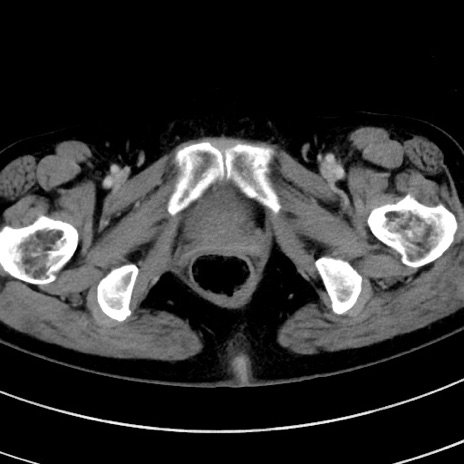

症例9(横断像)

【症例】 60歳代女性

【主訴】むかつき、みぞおちの痛み

【現病歴】3日前よりむかつきがあり、食事がとれない。

【既往歴】糖尿病

【身体所見】発熱なし、心窩部圧痛軽度あるも、腹膜刺激症状なし。

【データ】WBC 7400、CRP 1.92